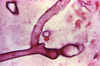

A man with diabetes mellitus has a headache, facial pain, a black necrotic facial eschar, and cranial nerve palsies. What is the likely diagnosis?

Cavernous sinus thromboses leading to cranial nerve involvement, a complication of Mucor and Rhizopus infections

Where are the abscesses in Mucor and Rhizopus infections most commonly found?

Rhinocerebral and frontal lobes